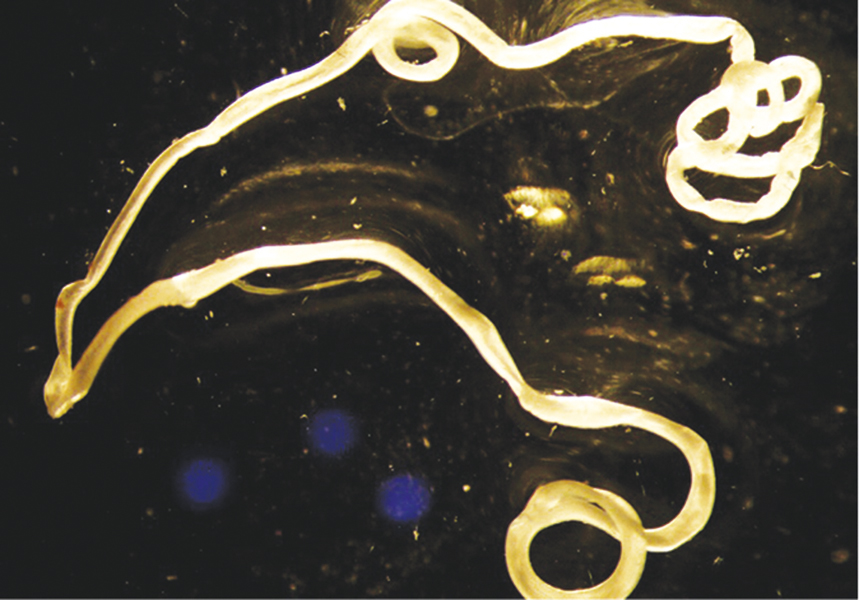

Fig. 5. Photo of the end area of the extracted D. repens female executed with a stereomicroscope digital camera

Рис. 5. Фото концевого отдела извлеченной самки D. repens, выполненноe цифровой камерой стереoмикроскопа

Fig. 6. Photo of a helminth executed with a stereomicroscope digital camera

Рис. 6. Фото гельминта, выполненноe цифровой камерой стереoмикроскопа